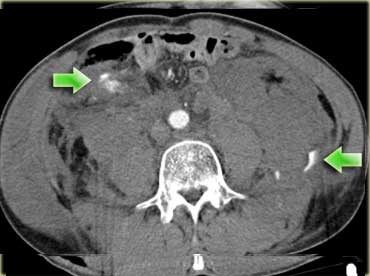

Các dấu hiệu bao gồm:

- Giảm tưới máu lách (mũi tên vàng).

- Nhiều vùng thoát thuốc cản quang (mũi tên xanh lá).

- Tràu máu ổ bụng và tràn khí ổ bụng.

- Nhiều đoạn ruột có thành dày lan tỏa (mũi tên xanh dương).